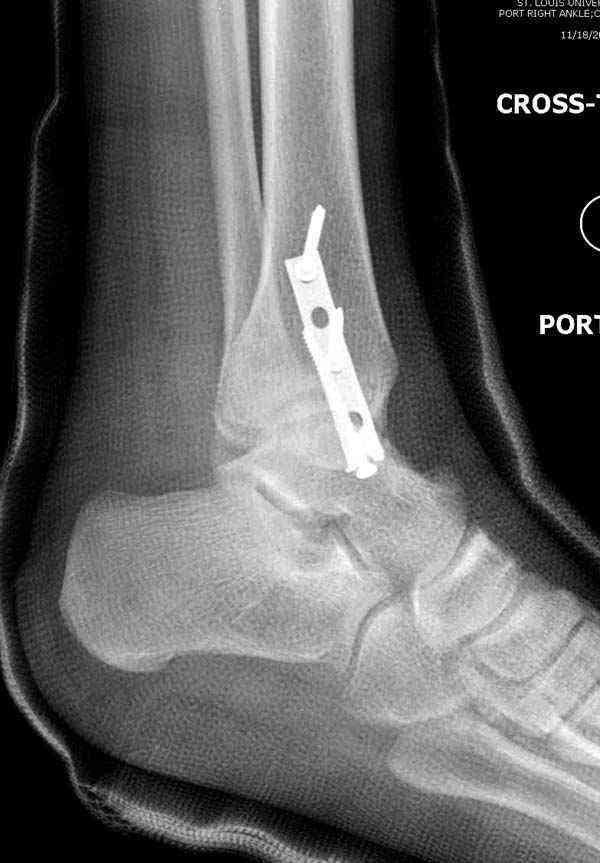

Нет первичных снимков, перелом очень низкий и под большим сомнением диагноз разрыва синдесмоза. Медиальная сторона отрепонирована на "хорошо" и, по-видимому, прорезание проволоки произошло во время операции. Без снимков трудно судить о высоте малоберцовой, а лодыжка находится в варусе. Лагирование получилось, но возле тонких шурупов передне-задний шуруп выглядит немного тяжеловато.

Во всех руководствах АО имеется описание техники применения низкопрофильных пластин 1/3 трубки, которые могут быть применены для фиксации наружной лодыжки. Фиксацию проводят кортикальными 3.5 мм шурупами, и если дистальная фиксация недостаточная, тогда усиливают конструкцию созданием hook plate. Сгибая конец пластины на последнем отверстии, внедряют его в дистальный отдел, и тем самым создается дополнительная фиксация.

Современные преконтурированные пластины не имеют таких недостатков, и разделяются на правые и левые, а также на латеральные и задние. Множественные дистальные шурупы 2.7 мм уменьшают подкожное раздражение, и такой имплант можно оставить на долгий срок без удаления.

Здесь несколько частных случаев: перелом голеностопа со сравнительными снимками и разрыв синдесмоза, а также медиальная Hook пластина.